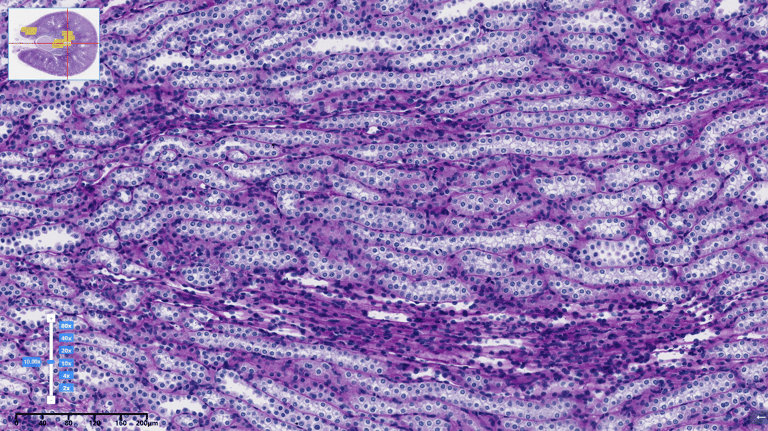

HISTOLOGY

Tissue grossing, embedding, and sectioning

Routine H&E and special staining